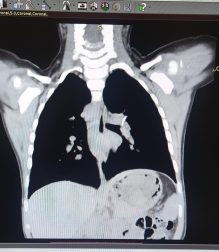

Bakıda 2 yaşlı körpə bir il nəfəs borusunda sümük parçası ilə yaşayıb - FOTO

Bakıda 2 yaşlı körpə bir il nəfəs borusunda sümük parçası ilə yaşayıb.

O qeyd edib ki, 2 yaşındakı qız bir il nəfəs borusunda sümük parçası ilə yaşayıb:

"Artıq çətinliklə nəfəs alırdı, xırıltı uzaqdan eşidilirdi. Körpənin 1 yaşı olanda balıq yediyini deyirlər və ondan sonra qızdırma öskürək, xırıltı başlayıb. Aparılan bütün müalicələrə baxmayaraq xırıltı, öskürək getdikcə artırdı və tez-tez temperaturu yüksəlirdi. Valideynləri vəziyyətinin getdikcə pisləşdiyini və vəziyyətinin ağırlığı ilə əlaqədar müraciət etdikləri klinikalarda qəbul etmədikləri üçün bizim klinikaya müraciət etdilər. Ciddi risk daşısa da, körpənon rahat nəfəs alması üçün sümüyü nəfəs borusundan çıxarmaq məcburiyyətində idik. Bronxoskopiya işıqlı alətlə nəfəs borusuna girilərək çətinliklə olsa da, sol ana bronxdan sümüyü problemsiz çıxartdıq. Nəhayət ki, 1 ilin sonunda balaca qızımız rahat nəfəs almağa başladı".